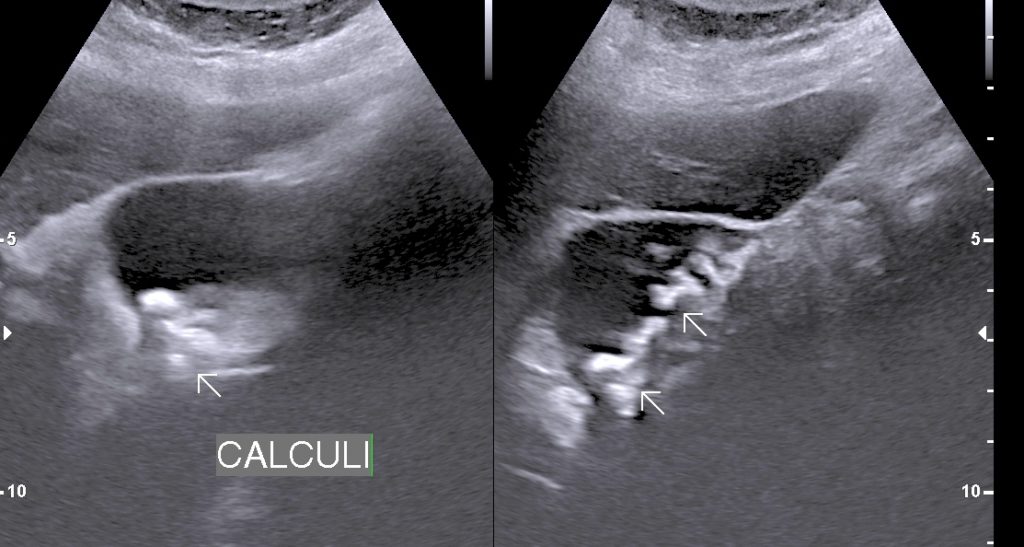

• Cholecystitis: Cholecystitis is Inflammation of gall bladder. Acute calculus cholecystitis results when calculus/calculi get impacted at neck of gall bladder or cystic duct.

• Finding: Sonography shows thickened oedmatous walls of gall bladder & impacted calculi. Sludge, pericholicystic fluid , localized abscess are additional findings. Sometimes gall bladder is so overdistended that impacted calculi may not be visualized.